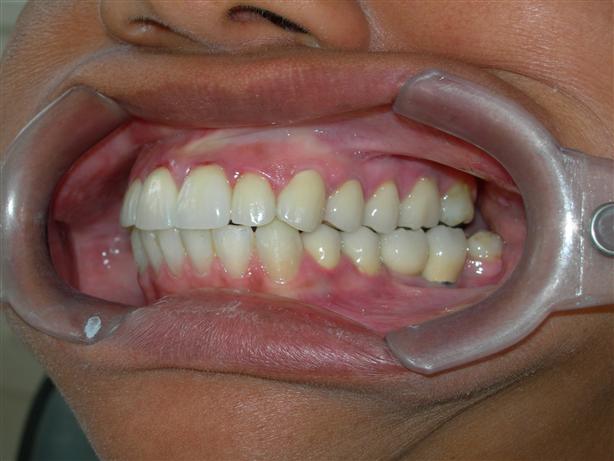

Caso concluído com próteses

metalocerâmicas cimentadas